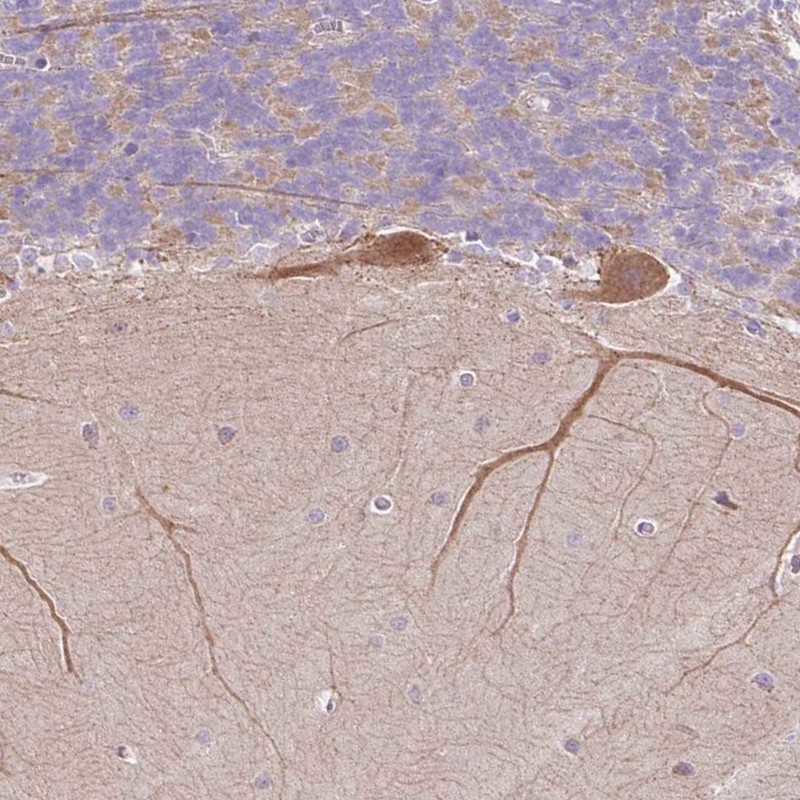

Immunohistochemical staining of human cerebellum shows moderate cytoplasmic positivity in Purkinje cells.